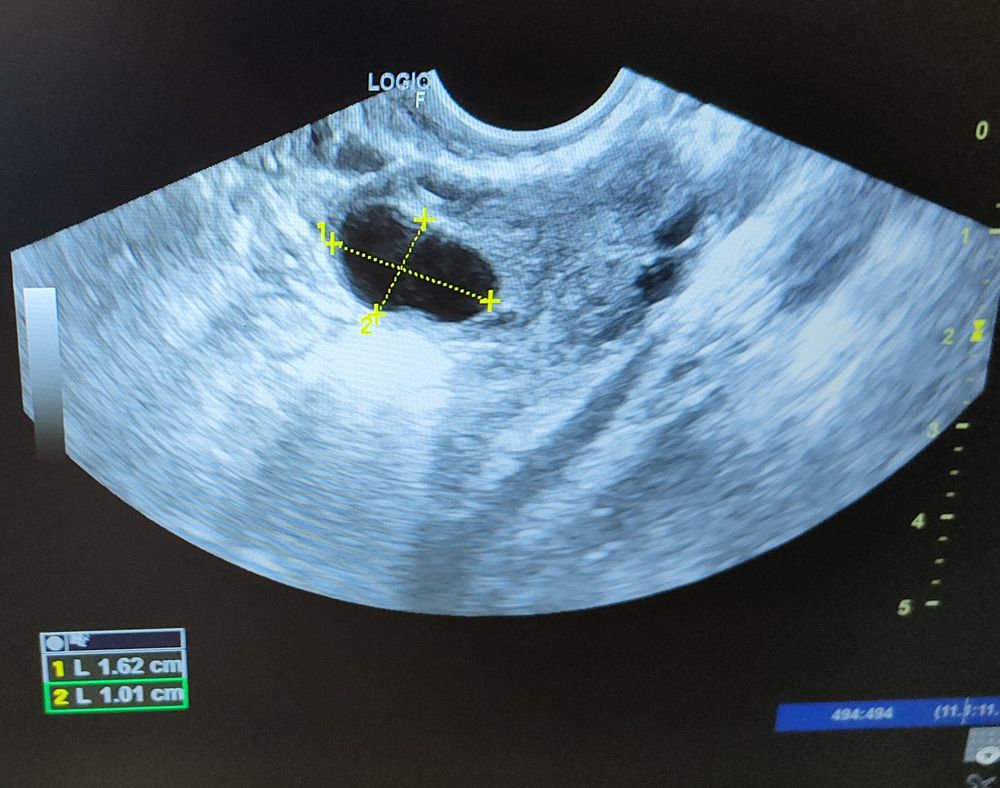

Девочки, что вы видите, узистка нормально не посмотрела, сказала овальный фолликул, 16.2 на 10.1, эндомитрий 7.3. Я вижу 2 маленьких фолликула.